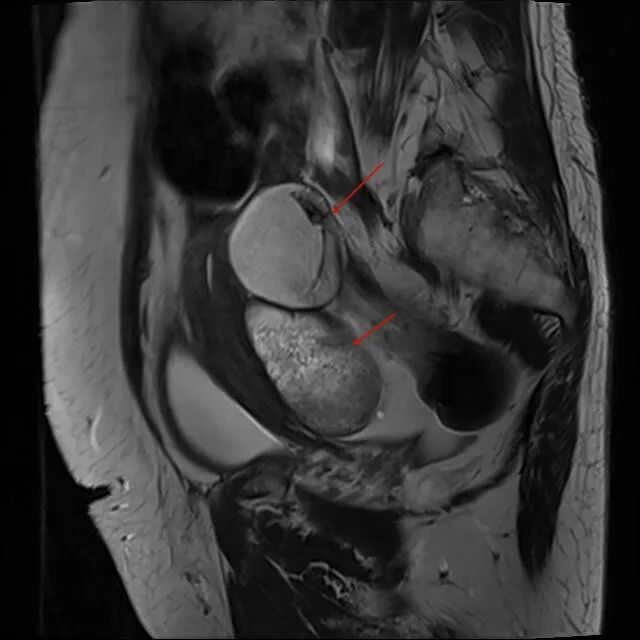

福建省肿瘤医院妇科肿瘤外科与胃肠肿瘤外科协作,一次手术成功完成卵巢与胃的双发肿瘤切除。 术后,患者恢复顺利康复出院。 王女士(化名)今年66岁,2周前因下腹闷痛就诊当地医院,上腹部CT提示: 胃体小弯侧外侧缘肿块,考虑胃外生性间质瘤可能,肿大淋巴结待除; 胃体小弯外侧缘见一类圆形肿块,肿块向外 与胃体壁关系密切,胃左动脉紧贴肿块表面 盆腔磁共振检查提示:盆腔多发囊实性肿物,双侧卵巢肿瘤可能性大(左侧10.9cm×12.3cm,右侧7.3cm×7.4cm)。 子宫双附件区,左右两侧都可见 多房囊实性肿物,子宫受压、前移 面对这一结果,王女士及家属有些不知所措,不知是先处理胃部肿物,还是先处理巨大的盆腔肿瘤。经多方打听后,王女士在家人陪同下,慕名前往福建省肿瘤医院副院长、妇科肿瘤外科孙阳教授门诊。 经过详细询问,孙阳教授了解到,王女士于30年前曾罹患颅脑恶性肿瘤并进行了手术及放疗治疗,这次检查发现的胃部肿块表面紧贴胃左动脉,且合并盆腔巨大肿物,病情复杂,手术风险较大。 在每周例行的妇科肿瘤多学科诊疗(MDT)讨论会上,孙阳教授主持了妇科肿瘤外科、腹部肿瘤外科、影像科、麻醉科及重症医学科等专家,对王女士的病情进行了多学科诊疗(MDT)讨论。专家们认为,王女士胃部的肿物较小,可通过微创(腹腔镜)手术将肿瘤切除;而盆腔肿瘤巨大,在保证肿瘤不播散、无瘤原则的基础上,若要完整彻底切除,则需进行开腹手术。 为了避免患者经历两次手术,减少相关并发症的发生及医疗费用,团队充分评估后决定:妇科肿瘤与胃肠肿瘤外科协作联合开展手术,“一次手术,将两种肿瘤解决”。 手术首先由胃肠肿瘤外科杨春康主任医师行腹腔镜胃小弯侧肿物切除术,在上腹部手术完成后,由妇科肿瘤外科孙阳教授行下腹部的经腹盆腔巨大肿物切除术+全子宫切除术。手术过程顺利,肿瘤被完整切除,术中出血不到100ml。 术后第2天,患者排气并能下地活动,恢复顺利。女子同时查出两种肿瘤不知道该先处理哪个